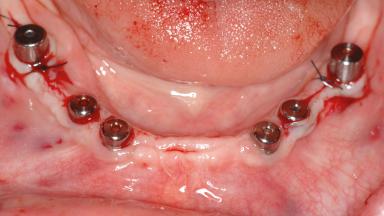

Le Fort I Interpositional Graft and Mandibular Sandwich Osteotomy for Maxillofacial Rehabilitation after Severe Periodontitis

A 47-year-old woman who had suffered from aggressive periodontitis requiring a number of periodontal interventions over more than 10 years was referred by her general dental practitioner and periodontologist for bone augmentation and implant therapy. Her failing dentition had already been scheduled for extraction. The patient expressed a desire for implant-supported fixed restorations and esthetic improvement of her lower face. She had agreed to consult with a maxillofacial surgeon after the referring dentist had suggested bone augmentation. An initial examination by the maxillofacial surgeon revealed mobility of all residual teeth in a patient who was very unhappy with the function of her removable partial dentures. Due to periodontally migrated flaring teeth and loss of occlusal support, the vertical dimension of occlusion was dramatically reduced. The patient was displeased with her lower face because of deepened nasolabial, commissural, and supramental folds.

# of Implants 14

Type of Implants Two-Piece

Defining Characteristics Fully edentulous upper jaw to be rehabilitated with four or more implants

Modality Fixed hybrid bridge on 5+ implants